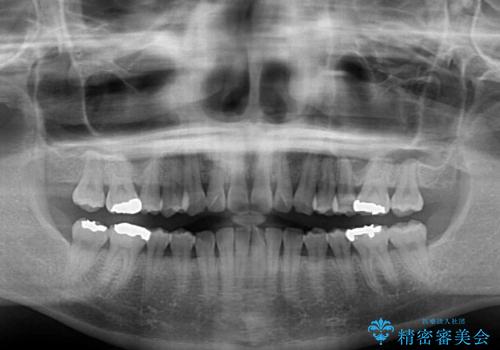

- 前歯のデコボコを気にして来院された患者様です。

歯列不正が軽度であり、インビザラインの装着時間を遵守してくださったため、日本と海外を行き来しながらも2年弱でしっかりと仕上げることができました。